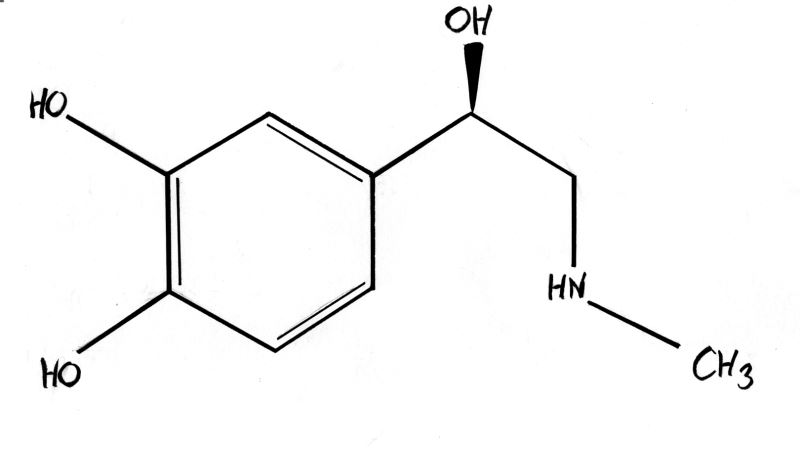

fenilalanin- tirozin amino asitleri: aminoasitler arasında özellikle tirozine karşı bi hayranlığım var. neredeyse her taşın altından(abartıyorum) çıkan bir aminoasit. öncelikle fenilalanin ve tirozinin moleküler yapısından bahsetmem gerekir. bu iki aminoasit halkasal bir radikal gruba sahiptir. bu grup benzen halkasının türevleri olan fenil ve fenol gruplarını taşır. ve hormonlar nörotransmitterler ve sitokinler arasında benzen fenol ve fenil halkası bulunduran tüm yapılar tirozin ve fenilalanin aminoasitlerinden sentez edilir.

bunları fotoğraf ile göstereyim:

şu gördüğünüz adrenalin ve yine aynı halkasal yapıyı görüyorsunuz

evet... bu hormonların hepsi tiroksin aminoasitinden sentezlenir. çünkü tiroksin aminoasitinden bu halkasal yapı alınarak başka moleküller ile birleştirilip bu hormonlar oluşturulur. bu halkasal yapılar, benzen, fenil- fenol ve benzeri yapılar şeker, yağ gibi besinlerde bulunmaz. yalnız tirozin ve fenilalanin aminoasitinden elde edilebilir. dışarıdan almak zorundasınız, zira vücudumuzun bu molekülleri sentezleme yetenekleri yoktur-sınırlıdır. ve bu aminoasitler olmadan bu adı geçen hormonları sentezleyemezsiniz. bu da vücudunuzun genel işleyişini bozarak ciddi metabolik hastalıklara yol açacaktır.